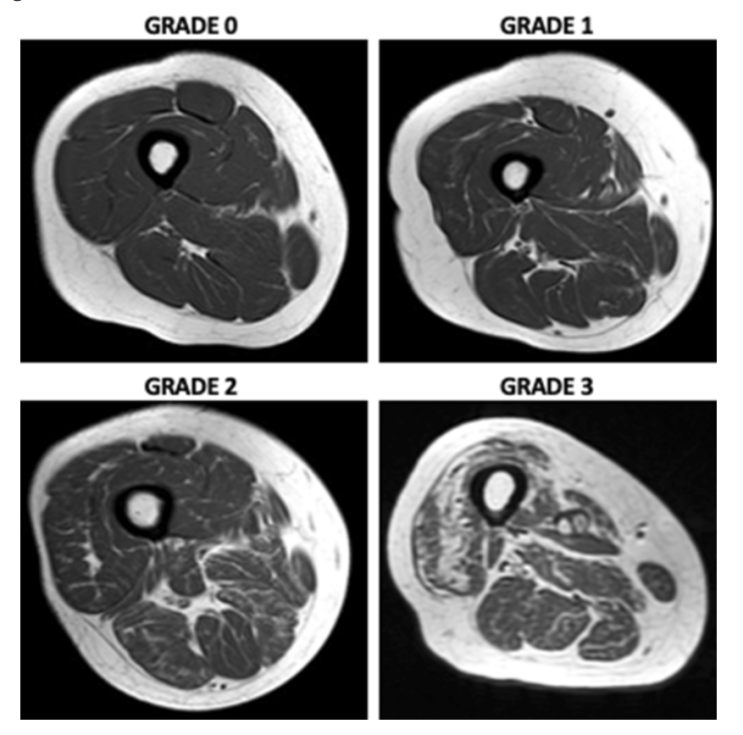

연금부자보다 근육부자 되세요 (근감소증)

근감소증은 나이가 많아지면서 근육의 양, 근력, 근 기능이 모두 감소하는 질환을 의미합니다. 나이가 들면...